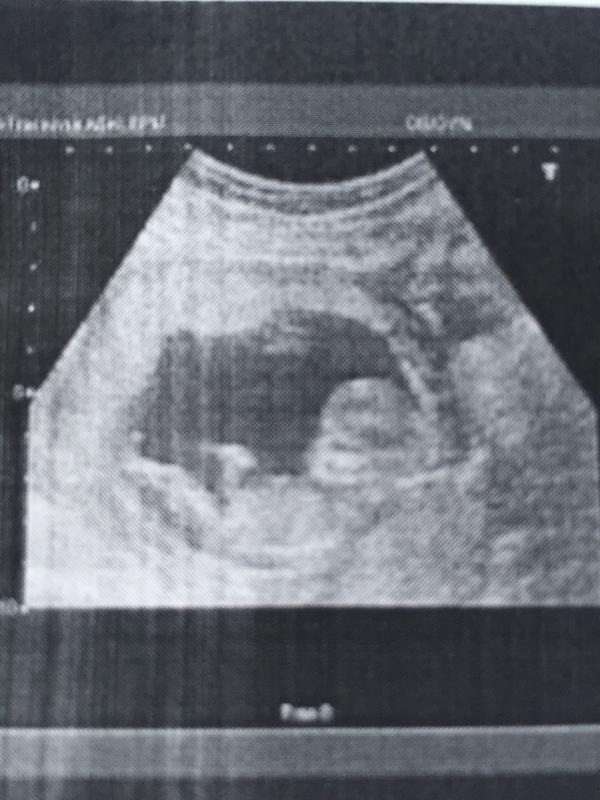

Сходили мы на скрининг,результаты анализов будут через пару дней,на УЗИ встретились с нашим мальчиком(как сказала узистка),какой же он у нас крутой,ручками машет,ножками машет....мой пузожитель любимый